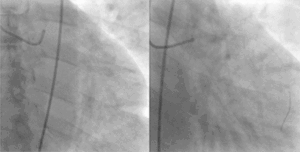

![]() A coronary angiogram showing the circulation in the left main coronary artery and its branches. | |